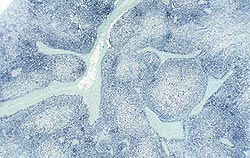

| Quantité modérée | |

| Faible quantité | Quantité élevée |

Quantités faible, modérée et élevée de génome de PCV2 dans les organes lymphoïdes. Les deux images de droite correspondent à des cas de MAP. Technique d’hybridation in situ.